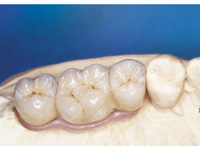

Velká mezera

V případě chybění většího počtu zubů v postranních úsecích čelistí je možné ošetření pomocí implantátů, které nahradí ošetření pomocí snímacích náhrad kotvených na zbývajících zubech nebo patře.

Podmínkou je opět dostatečné množství kosti.

Protetické řešení může být pomocí můstku, který je kotvený na implantátech nebo pomocí jednotlivých korunek na implantátech.

V zásadě je možné do těchto můstků zařadit i přirozené zuby, zejména pokud je potřeba tyto zuby ošetřit proteticky - korunkami. Korunky nebo můstky mohou být na implantáty nacementovány nebo přišroubovány.

Zdravé zuby zůstanou zachovány a přitom náhrady jsou pevné, jako na vlastních zubech